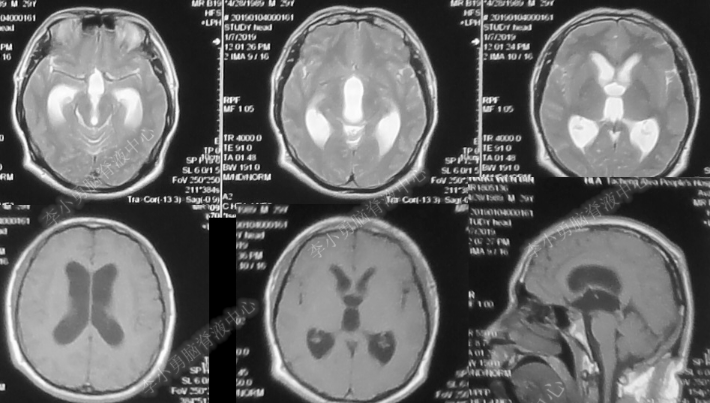

患者于2019年1月出现间断头晕,每天发作1-2次,持续数秒缓解,同时伴有右眼视力下降。到当地的新疆塔城地区某医院行头颅CT及MRI(图-1、图-2)检查发现脑积水。医生给甘露醇等药物治疗后,自觉头晕暂时减轻。

图-1:2019年1月3日头CT

图-2:2019年1月7日头核磁

图-3:2019年1月11日头核磁